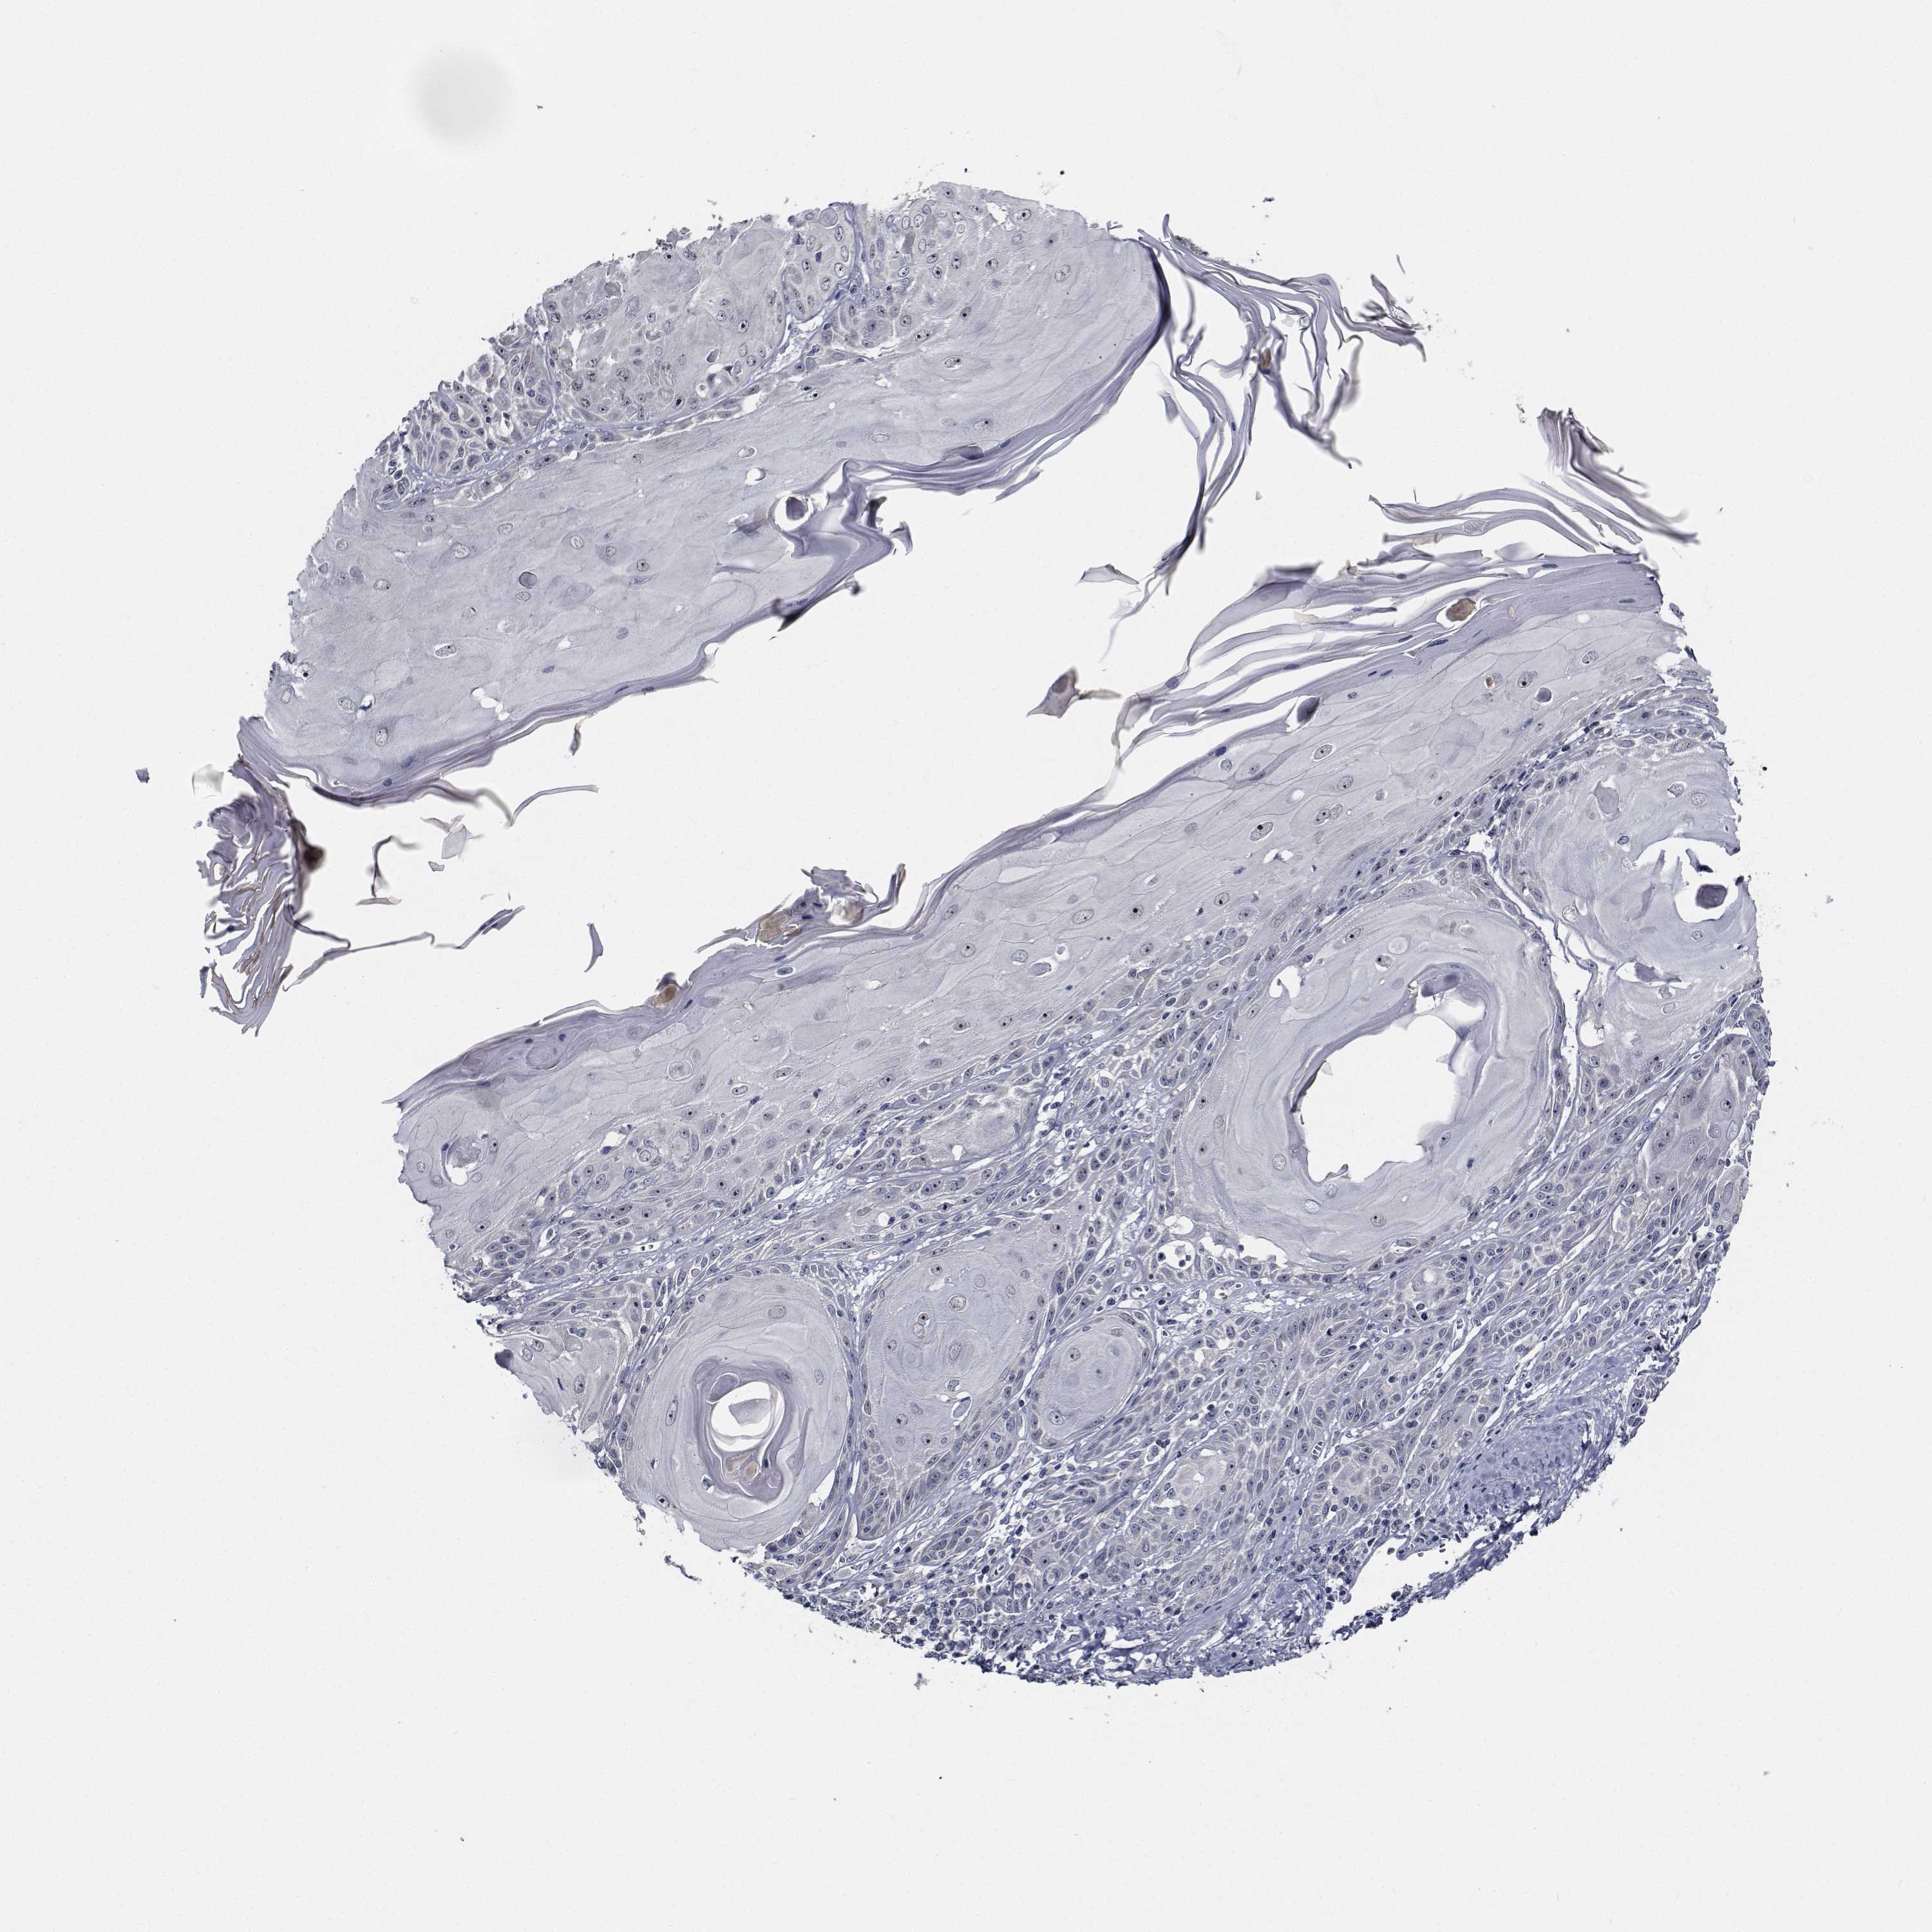

CANCER SKIN CANCER Show tissue menu

Basal cell and squamous cell cancer

SKIN CANCER - Protein expressioni

A mouse-over function shows sample information and annotation data. Click on an image to view it in a full screen mode. Samples can be filtered based on level of antibody staining by selecting one or several of the following categories: high, medium, low and not detected. The assay and annotation is described here.

Each image is clickable and will lead to virtual microscopy that enables deeper exploration of all samples and also displays staining intensity scores, fraction scores and subcellular localization as well as patient and tissue information for each sample.

Antibody HPA028224

Squamous cell carcinoma, NOS